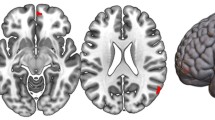

Meta-analysis of the continuous relationship between CT and schizotypy (n = 3004) revealed positive correlations between higher schizotypy and greater thickness of the medial orbitofrontal cortex/ventromedial prefrontal cortex (mOFC/vmPFC) (left: r = 0.057, punc = 0.004, 95% CI [0.02–0.09]; right: r = 0.067, punc < 0.001, 95% CI [0.03, 0.10]) as well the frontal pole (left: r = 0.046, punc = 0.021, 95% CI [0.01, 0.08]; right: r = 0.050, punc = 0.007, 95% CI [0.01, 0.09]) (Fig. 1A, Table S17). The positive association between greater right mOFC/vmPFC thickness and higher schizotypy remained significant after FDR correction (r = 0.067, pFDR = 0.02) (Fig. 2A/C). Moderator analyses did not reveal any significant effects of type of schizotypy questionnaire, FreeSurfer version, number of scanners or scanner field strength on the associations between CT and schizotypy (all pFDR > 0.05) (Tables S10–S13).

Abbreviations of the cortical regions are adopted from the brainGraph package and shown for regions with the most positive and negative effect sizes (r): FUS fusiform gyrus, ITG inferior temporal gyrus, iCC isthmus cingulate cortex, MOF medial orbitofrontal cortex, paraC paracentral lobule, pOPER pars opercularis of inferior frontal gyrus, periCAL pericalcarine cortex, rACC rostral anterior cingulate cortex, FP frontal pole, INS insula. L left, R right.